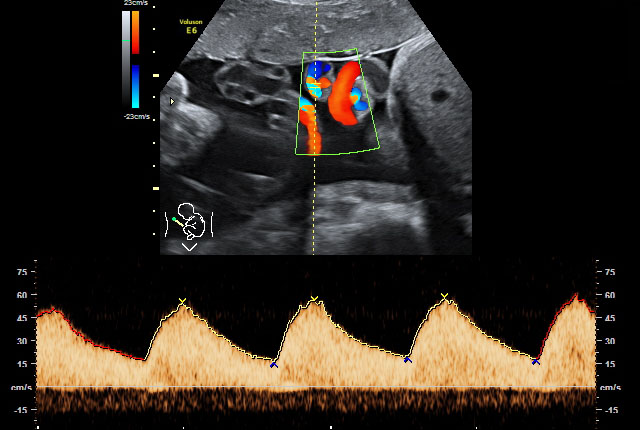

Wenn der Verdacht auf fetale Wachstumsstörungen und/oder fetale Fehlbildungen besteht, wird die Versorgungssituation des Ungeborenen durch eine spezielle dopplersonografische Untersuchung überwacht und die Funktion der Plazenta überprüft. Wir setzen hierbei den hochauflösenden Farbdoppler, also die sogenannte farbkodierte Doppler-Sonografie ein.

Bei der farbkodierten Doppler-Sonografie, einer bestimmten Form der Ultraschalluntersuchung, wird die Richtung des Blutflusses farblich dargestellt, um den Blutfluss in Arterien von dem in Venen unterscheiden zu können. Damit können auch Aussagen über das Ausmaß eventuell vorhandener Durchblutungsstörungen getroffen werden.